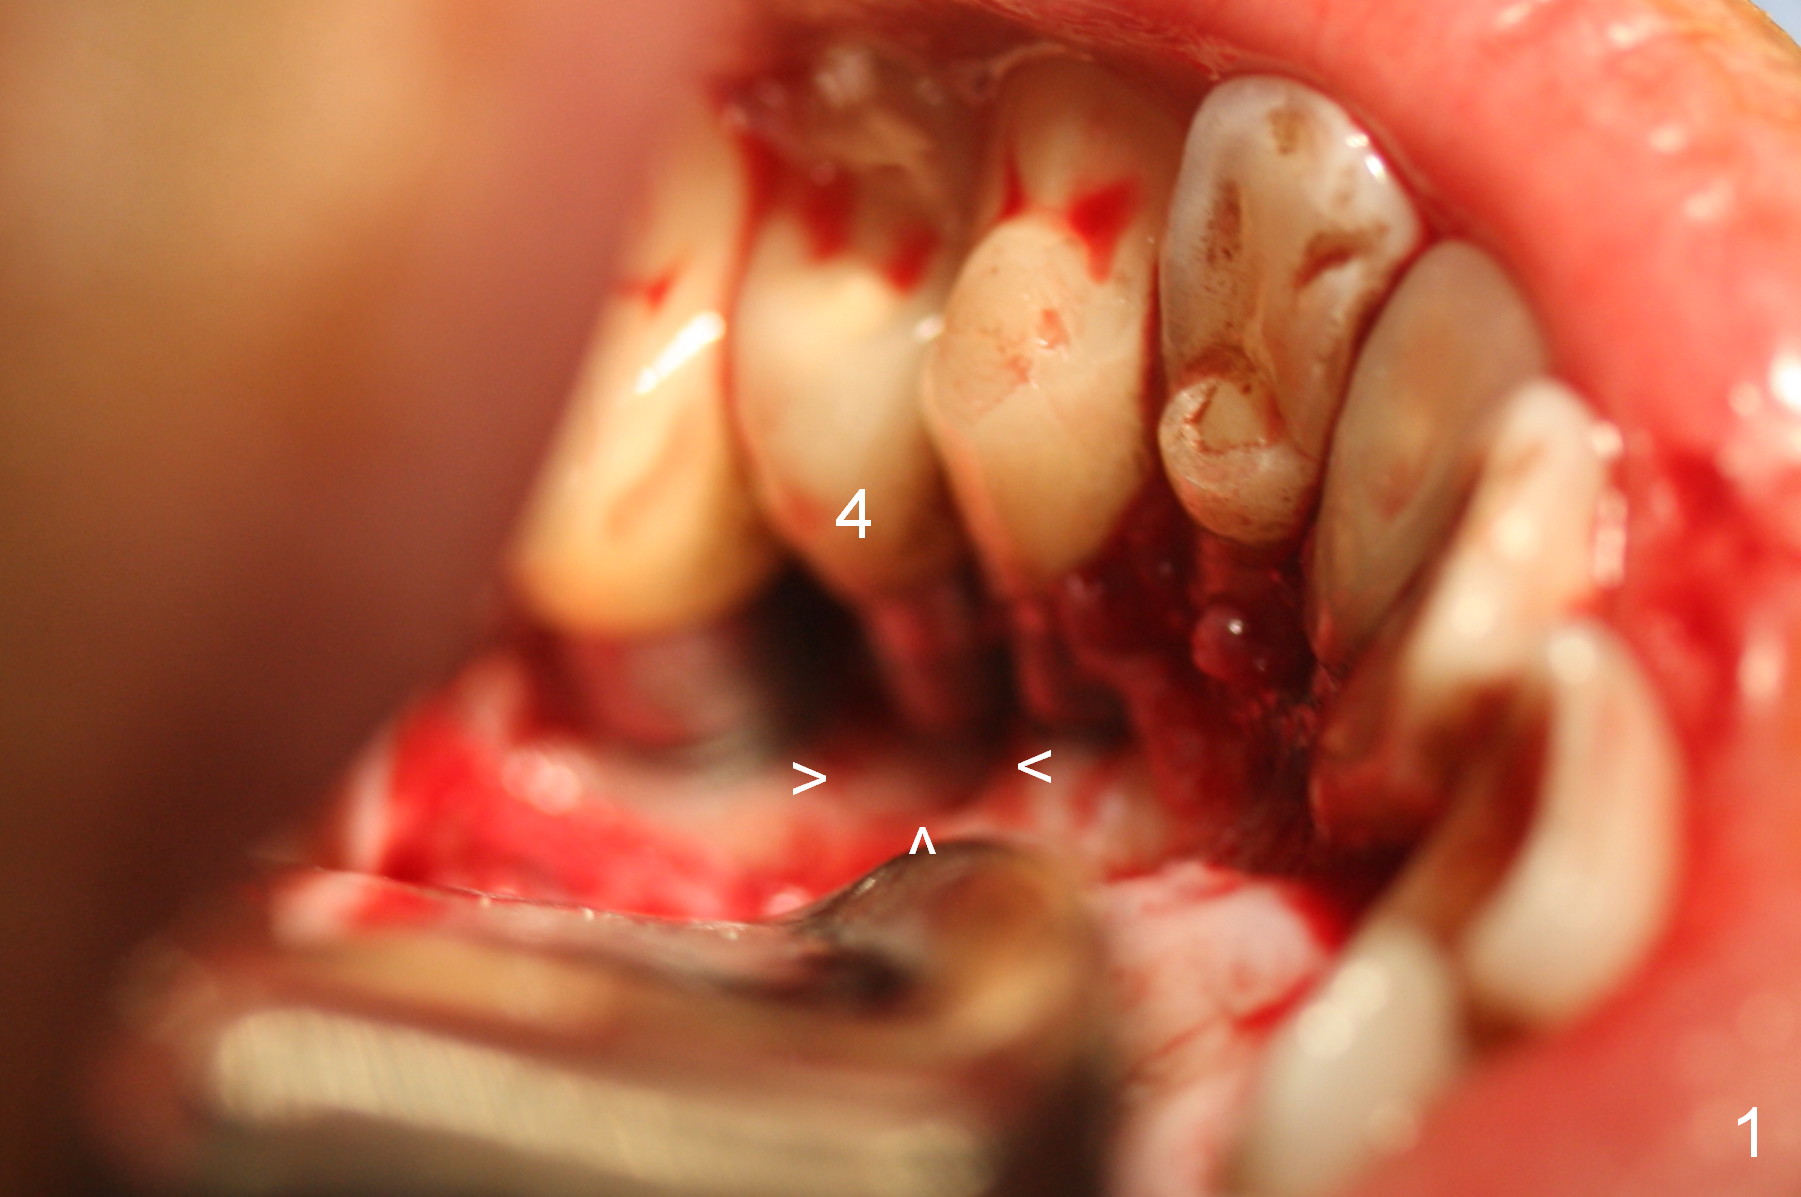

After reconfirmation of the deepest pocket between the implants at #3 and 4, a palatal sulcus incision is made with reflection of the flap. After granulation tissue curettage, a crater is found palatal to the implant at #4 (Fig.1 arrowheads), consistent with preop CT coronal section (Fig.3 *). Another complicating factor is excess temporary cement used for splinted provisional between #3 and 5 (Fig.2 *) between 0.5 and 4 months post #4 implant placement.